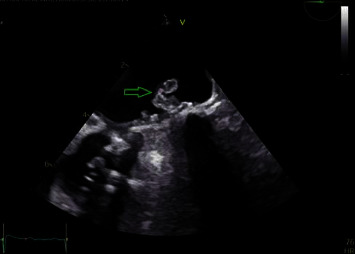

由副丝状念珠菌引起的人工瓣膜心内膜炎(PVE)导致的栓塞性中风是一种罕见的严重并发症。成功的治疗需要内科和外科相结合的方法。我们介绍了一个在诊断和治疗念珠菌性 PVE 时充满复杂性的病例,强调了多学科方法的重要性。一名50岁的男性因眩晕和低烧到急诊科就诊,被发现患有小脑卒中,很可能是心源性栓塞引起的,患者有未控制的糖尿病史和双人工瓣膜病史。诊断具有挑战性,需要进行经食道超声心动图(TEE)检查,结果显示二尖瓣假体上附着两个植被。治疗包括抗真菌治疗,但手术因经济问题而受阻。由于真菌血症持续存在,患者被考虑使用 AngioVac 植被抽吸系统。最终,手术没有进行,患者出院时计划接受长期抑制性抗真菌治疗。

Embolic stroke due to prosthetic valve endocarditis (PVE) caused by Candida parapsilosis is a rare and serious complication. Successful management requires a combination of medical and surgical approaches. We present a case full of complexities in diagnosing and managing Candida PVE, emphasizing the importance of a multidisciplinary approach. A 50 year-old male presented to the emergency department with vertigo and low-grade fever and was found to have cerebellar stroke likely from the cardioembolic origin, and the patient had a history of uncontrolled diabetes and double prosthetic valves. The diagnosis was challenging and required transesophageal echocardiography (TEE) which showed two vegetations attached to the mitral valve prosthesis. The management involved antifungal therapy, but surgery was hindered by financial issues. The patient was considered for the AngioVac vegetation aspiration system due to persistent fungemia. Eventually, surgery was not performed, and the patient was discharged with a plan for long-term suppressive antifungal therapy.